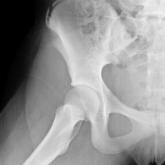

The Pop That Stopped the Soccer Game

In the middle of a soccer game, a 13-year-old girl felt her hip “pop” and had to be escorted from the field. Can you get her returned to play?